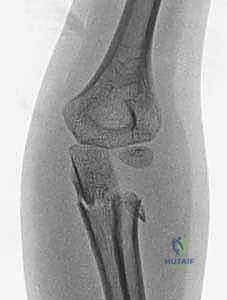

2. التصوير الشعاعي (X-Rays)

هو الخطوة الأساسية لتأكيد الكسر. يتم التقاط صور من زوايا متعددة (أمامية خلفية، وجانبية، ومائلة).

* علامة وسادة الدهون (Fat Pad Sign / Sail Sign): في بعض الأحيان، خاصة في كسور النوع الأول غير المزاحة، قد لا يظهر خط الكسر بوضوح في الأشعة. في هذه الحالة، يبحث الدكتور هطيف عن "علامة الشراع" أو ارتفاع وسادة الدهون المحيطة بالمرفق في الصورة الجانبية، والتي تدل على وجود نزيف مفصلي (Hemarthrosis) يؤكد وجود كسر خفي.